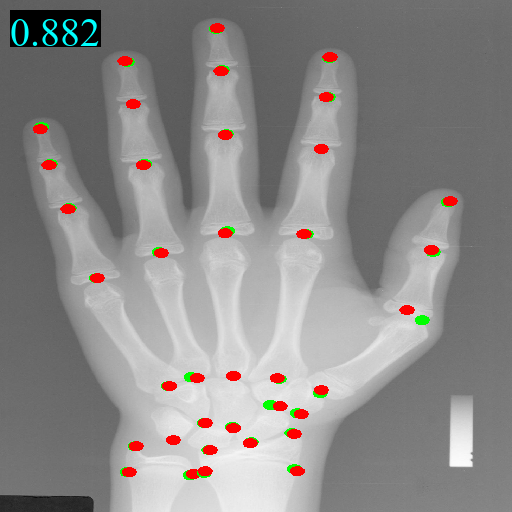

We take Model (f) which combines the above components as the final model. Model (f) using domain-adaptive transformer block and guidance network, beats any other models on all metrics by a huge gap. The predicted landmarks and heatmaps are exemplified in Figure 2.

Figure 2: Visualization examples of guidance heatmap Y~gsubscript~𝑌𝑔\tilde{Y}_{g}, fine heatmap Y~fsubscript~𝑌𝑓\tilde{Y}_{f}, output heatmap Y~~𝑌\tilde{Y} and images along with landmarks from four domains on head, hand, chest, and pelvis. The red points \bullet are predicted landmarks while the green points \bullet are annotated landmarks. The MRE value is on the top left corner of the image.